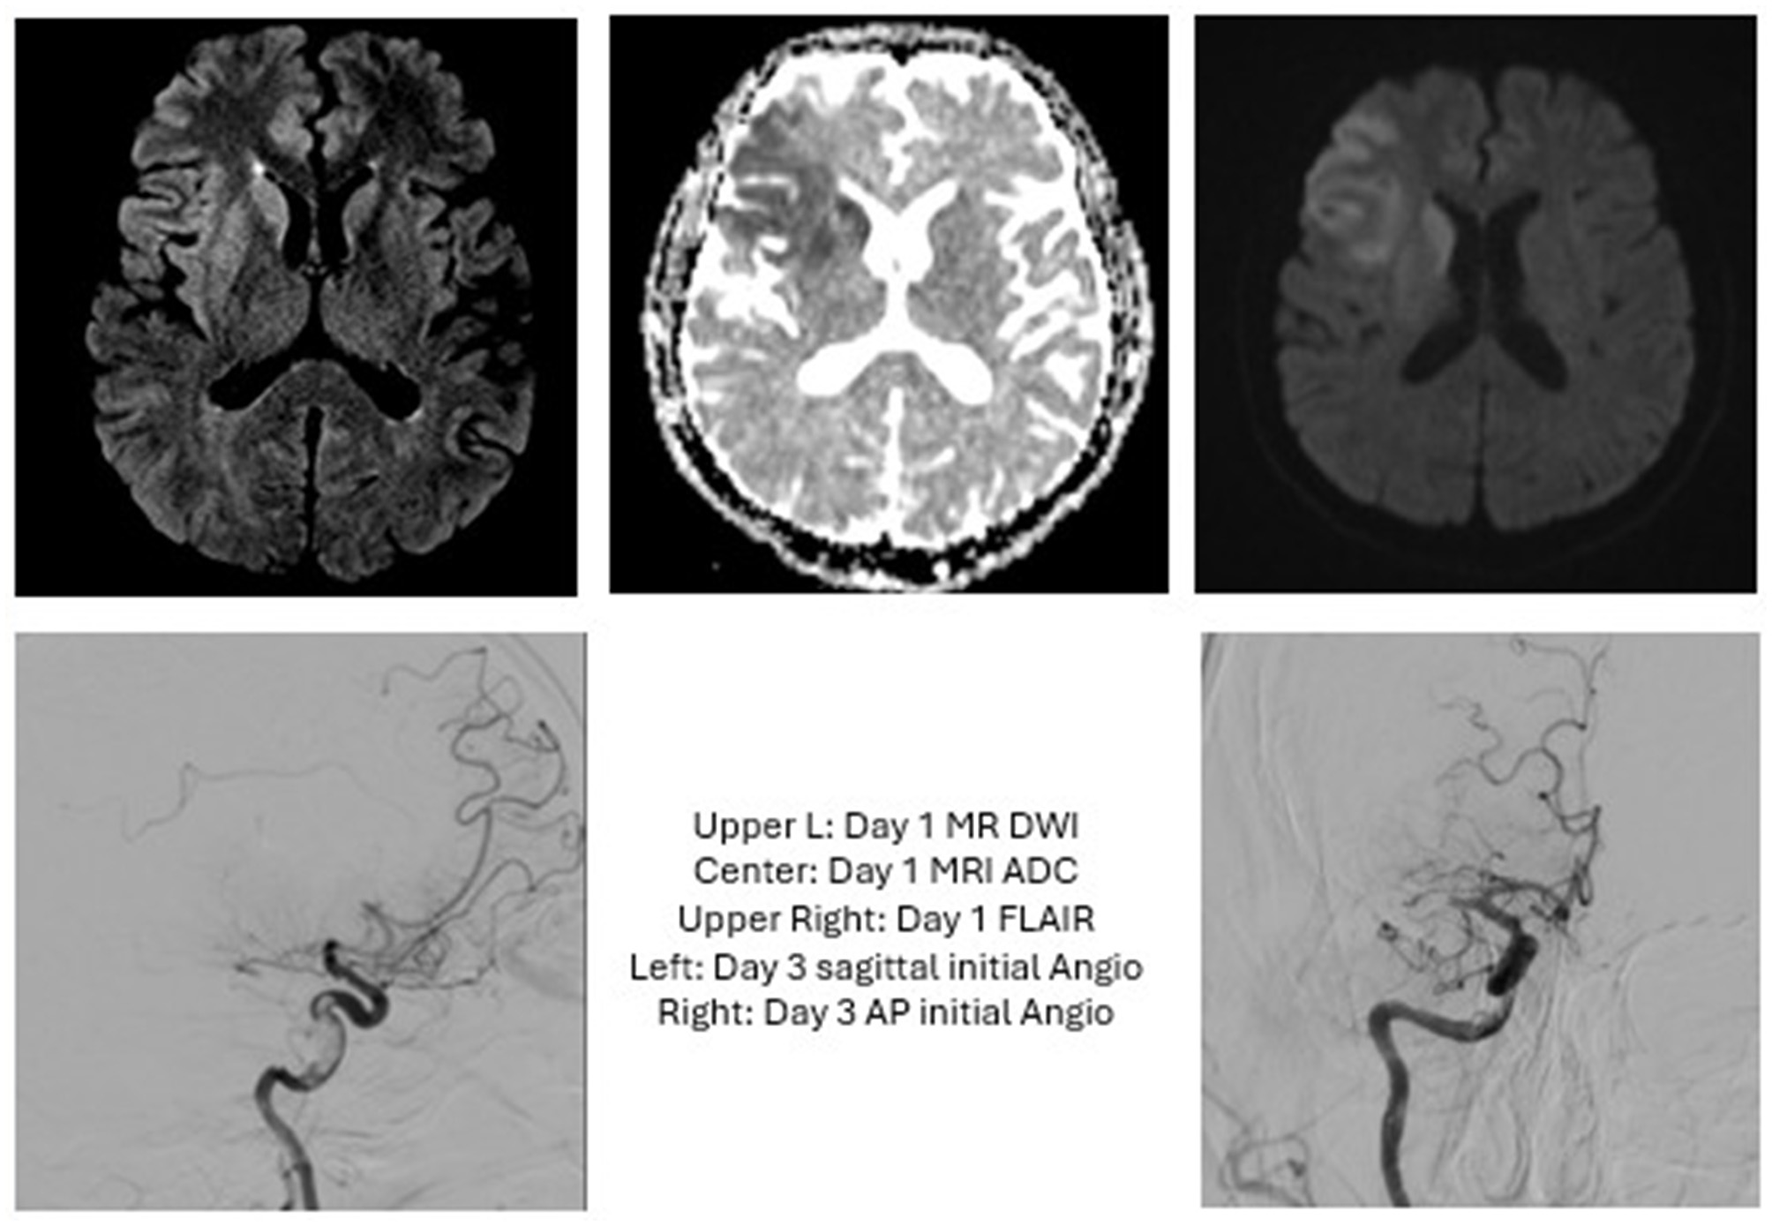

Figure 1

Case 1: The patient presented with an initial NIHSS of 7 and a R ICA occlusion but improved following administration of tPA. Heads Up testing in the IR suite revealed no further worsening, so MT was deferred. Three days later, the patient acutely worsened with NIHSS of 10 and an MRI showing R MCA occlusion. MT was performed with TICI 2C. Post-proceduraly, this patient required decompressive hemicraniectomy and was discharged with a tracheostomy and G-tube.